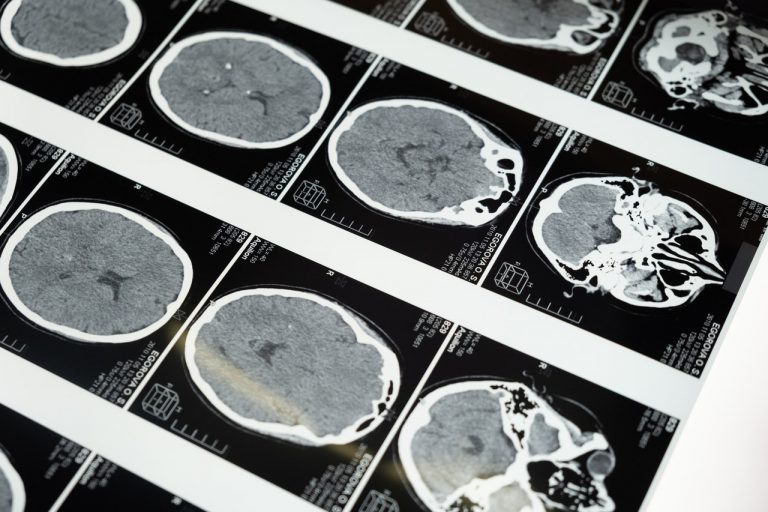

מרבית התביעות עוסקות באיחור באבחון גידול בעמוד השדרה. התובע התלונן על כאבי גב, אך הרופאים לא הפנו אותו לבדיקת MRI ולא ביצעו בדיקה נוירולוגית. בזמן שהגידול המשיך להתפתח, חלף זמן יקר. רק בשלב מאוחר עבר התובע ניתוח והקרנות, כשכבר נגרם נזק בלתי הפיך.

כעת על בית המשפט לבחון האם הרופאים פעלו בסבירות, או שמא התרשלו כשלא זיהו את תמרורי האזהרה בזמן.